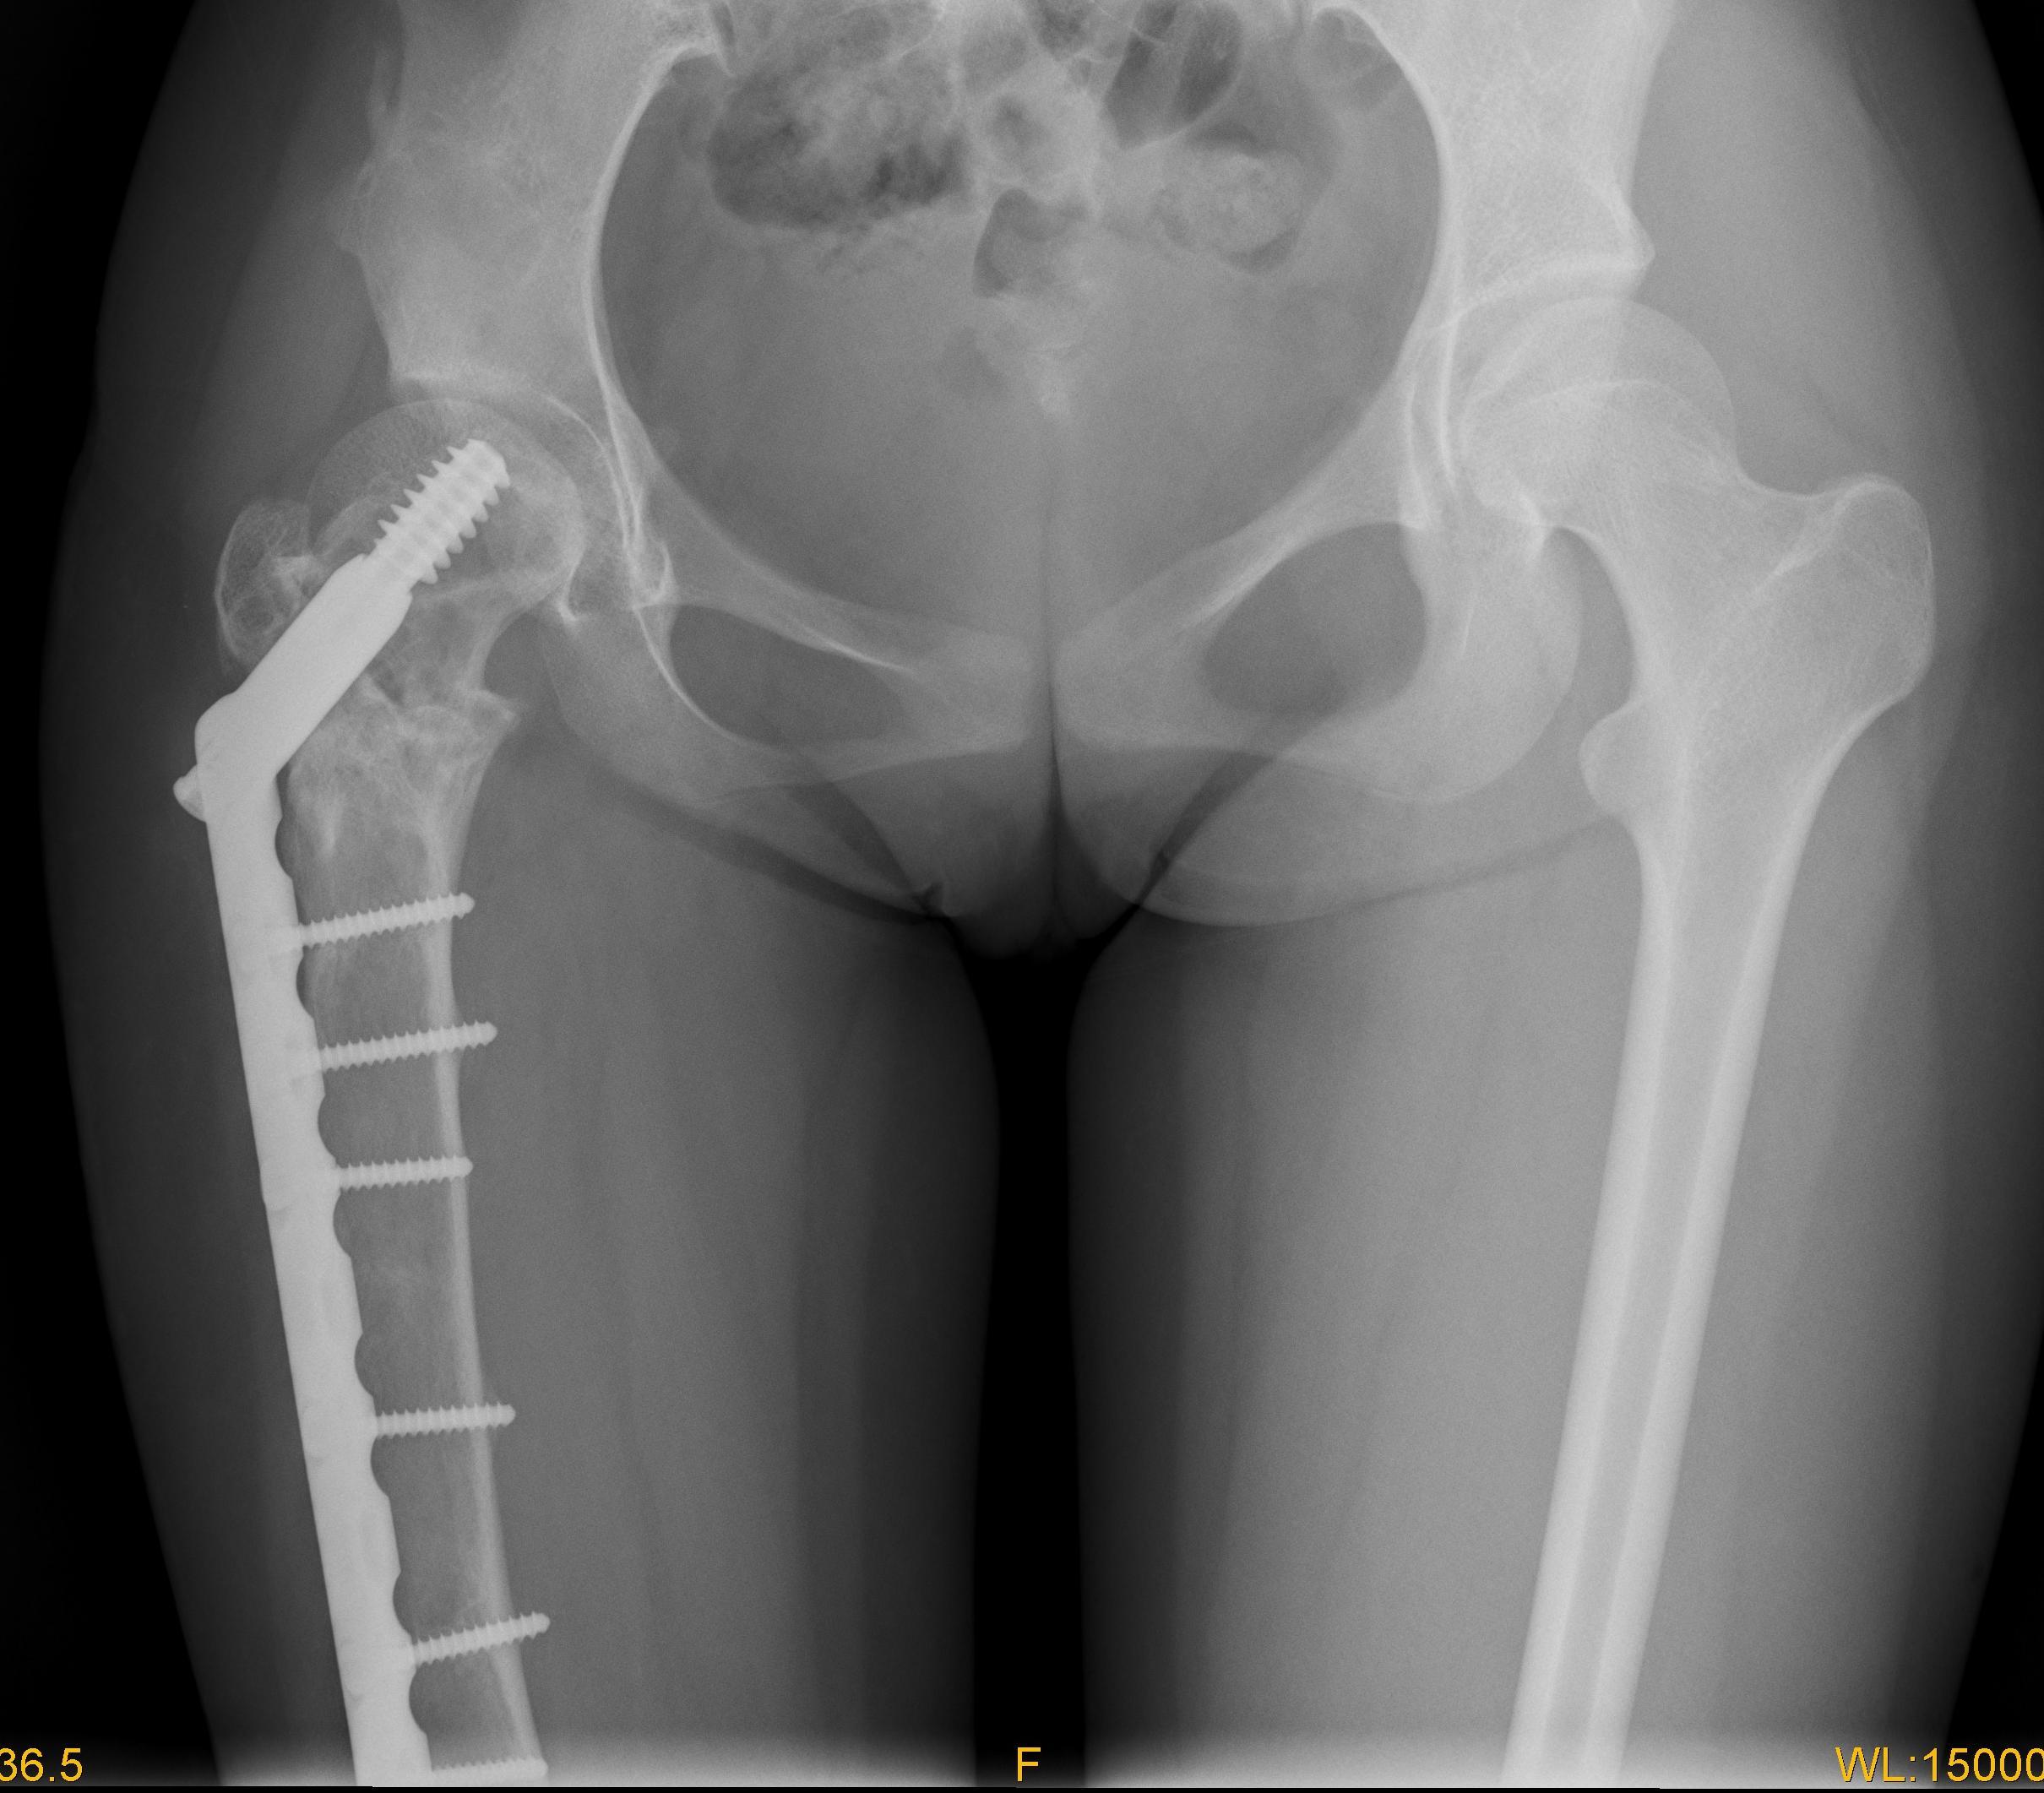

图4 女性,17岁,术前肢体短缩4cm图5 术后2年复查肢体等长,截骨处愈合

图6 女性,21岁,双侧DF 图7 术后5年力线正常,截骨愈合好